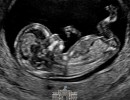

Este 25 de marzo celebramos el Día del Niño por Nacer, haciendo un llamado a proteger a quienes aún no tienen voz, reconociendo la dignidad inviolable de todo ser humano desde su concepción y ratificando la defensa de la vida como el primer derecho fundamental, del cual emanan… pic.twitter.com/v59QpvOhG2

Cada 25 de marzo se conmemora en nuestro país el Día del Niño por Nacer, una fecha dedicada a reconocer el valor de la vida humana desde su concepción y a promover su protección. En esta oportunidad, hacemos un llamado a proteger a quienes aún no tienen voz, reconociendo la dignidad inviolable de todo ser humano desde su concepción y ratificando la defensa de la vida como el primer derecho fundamental, del cual se desprenden todos los demás.